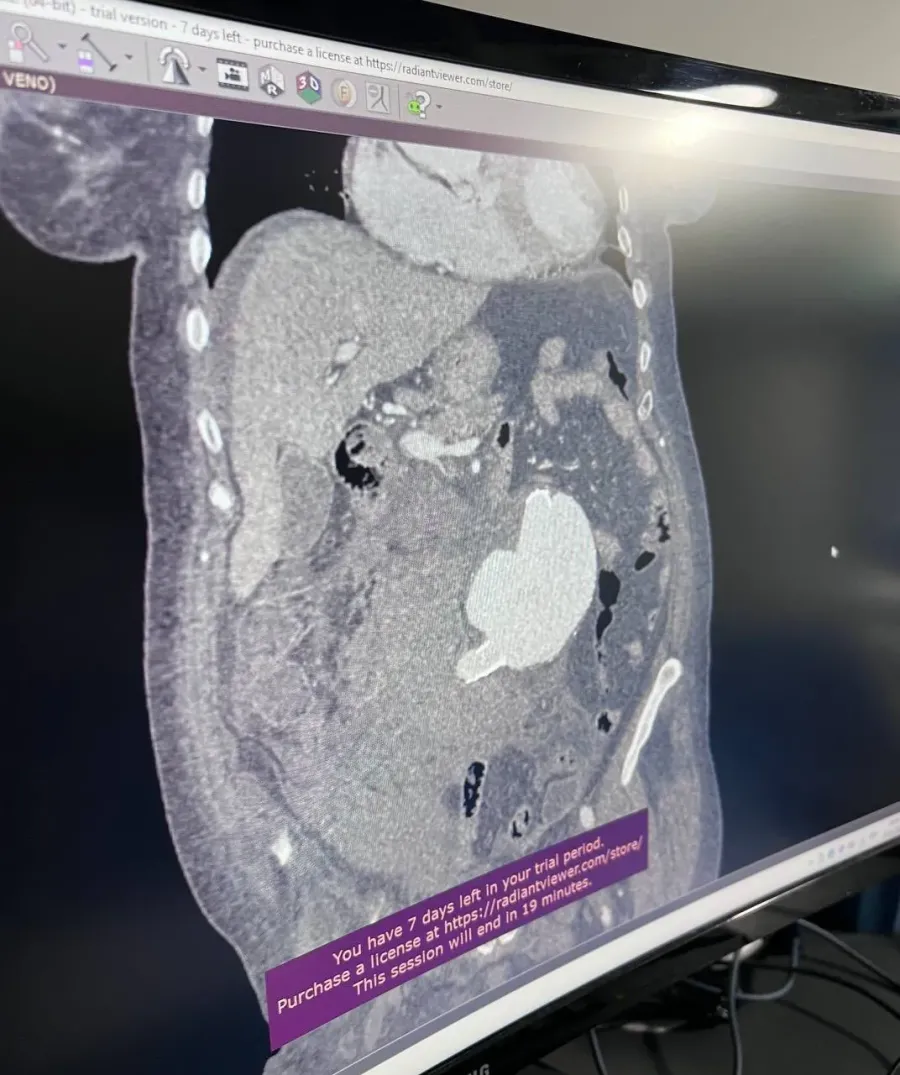

Тут вже чекала команда лікарів. Жінка втратила чимало крові — понад 3 літри, їй вливали донорську, а також власну кров, яка вилилась у живіт. З цим допоміг апарат для реінфузії, який після певної очистки може повертати власну кров пацієнтці. Операція тривала понад 4 години та пройшла успішно.